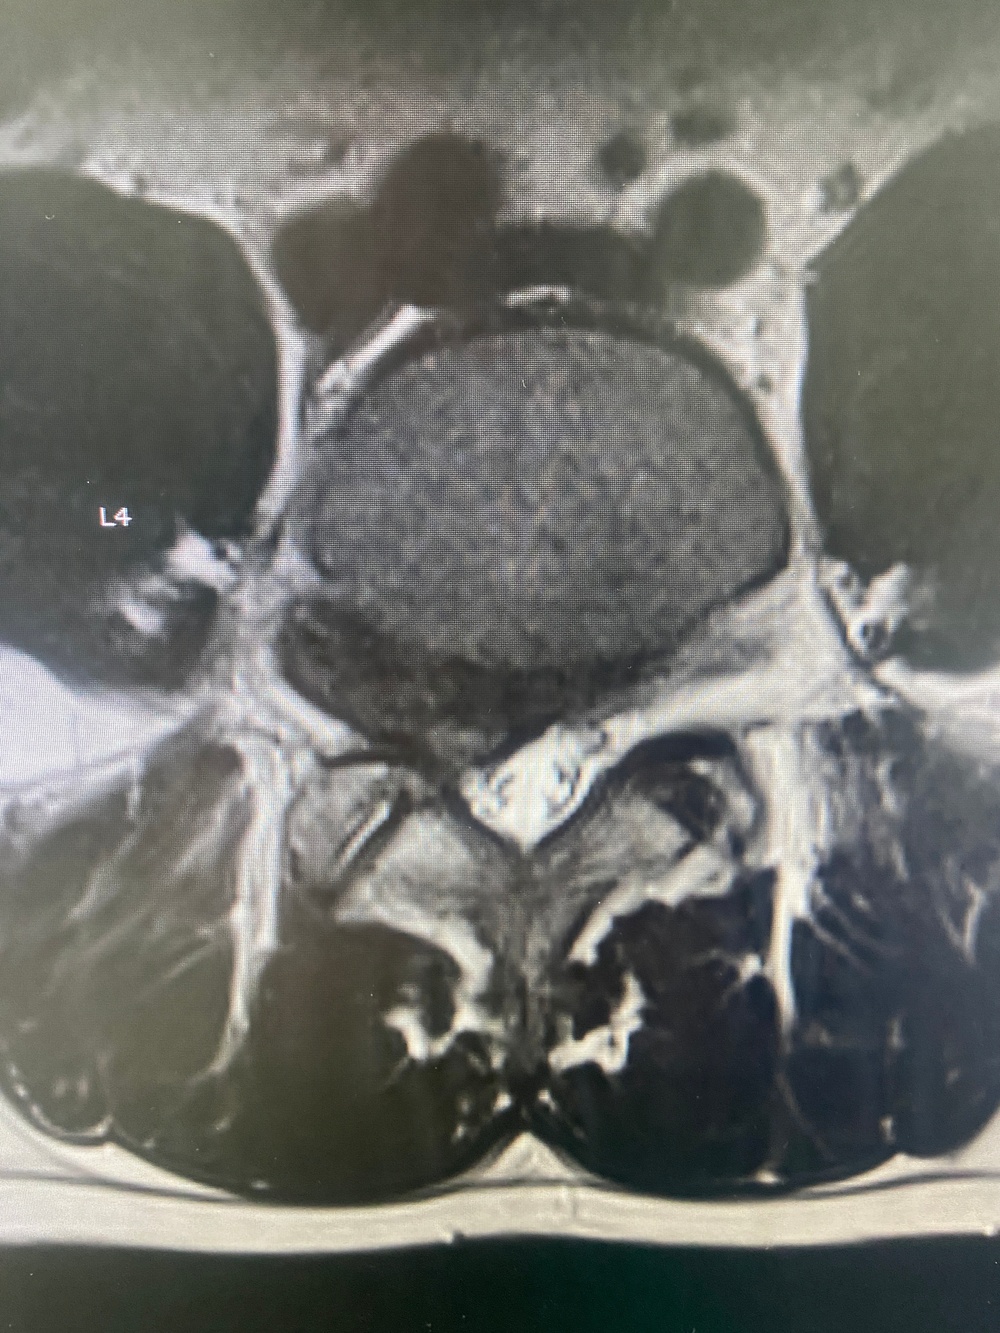

Advancing Spine Surgery in the Pacific: First Uniportal Endoscopic Procedure at Naval Hospital Okinawa [Image 4 of 5]

Advancing Spine Surgery in the Pacific:  First Uniportal Endoscopic Procedure at Naval Hospital Okinawa

260408-N-TW242-1006 Okinawa, Japan (April 10, 2026) Lt. Cmdr. Ki Chang a Navy Medical Corps Officer and Staff Neurosurgeon at Naval Medical Center San Diego performed the first uniportal endoscopic spine surgery at U.S. Naval Hospital Okinawa, explains the procedure. (U.S. Navy photo by Courtesy Credit)